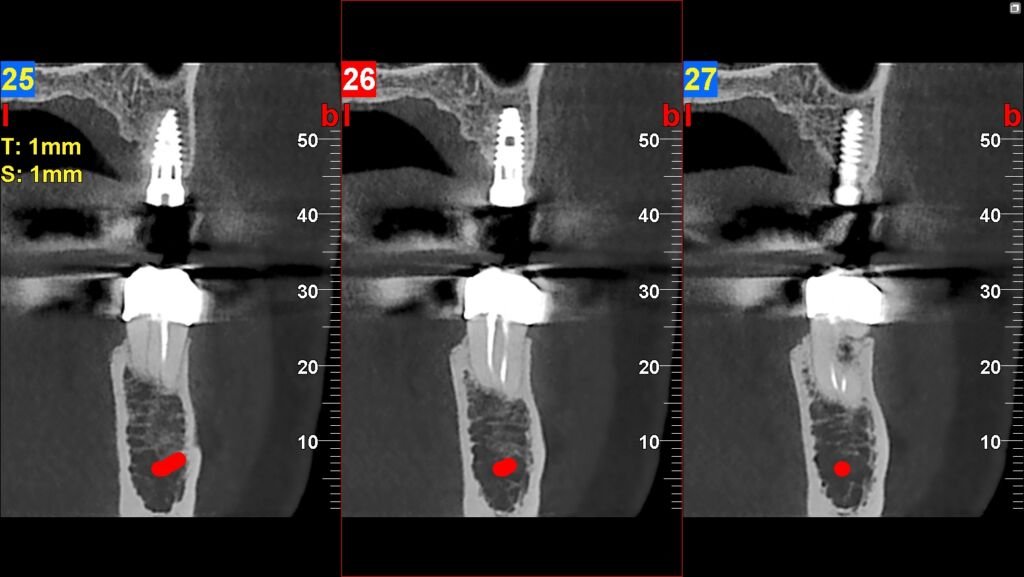

En TAC Facial somos especialistas en imágenes 2D y 3D para odontología, cirugía maxilofacial y evaluación facial. Brindamos claridad diagnóstica en cada estudio, asegurando que profesionales y pacientes cuenten con información precisa para planificar tratamientos con seguridad.

Nuestra tecnología Cone Beam 3D permite visualizar estructuras óseas y dentales con alta definición, favoreciendo diagnósticos exactos y resultados clínicos confiables.

Excelent soporte

"Trabajo con TAC Facial para todos mis pacientes que requieren estudios de implantes. Las imágenes son claras, precisas y la entrega es muy rápida. Definitivamente aporta seguridad al diagnóstico."

Dr. Marcelo M.

Implantólogo